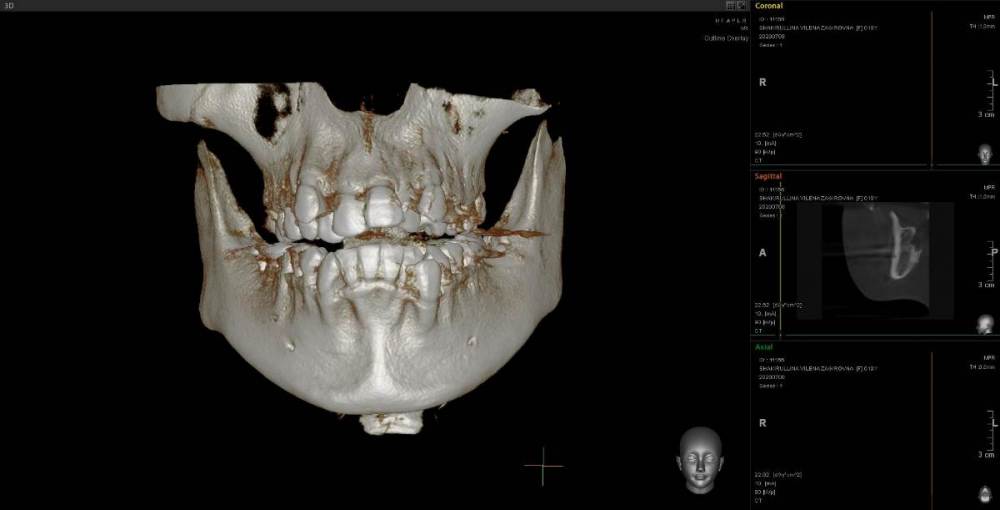

Женька Опубликовано 23 июня, 2021 Поделиться Опубликовано 23 июня, 2021 Коллеги, приветствую. Пришла пациентка с направлением на удаление 1.6-2.6 по ортодонтическим показаниям. Расспросив узнал, что принял решение такое ортодонт, тк премоляры интактны, а вот 1.6 эндодонтически пролечен. 2.6 с пломбой. Вопрос, оправдан ли такой подход? Есть лишь реконструкция КТ. Зубы я конечно не удалил, тк о таком подходе слышу впервые. Связавшись с ортодонтом узнал, что нестандартное удаление... Что думаете? p/s мудрые почему-то пока не удаляем... Ссылка на комментарий